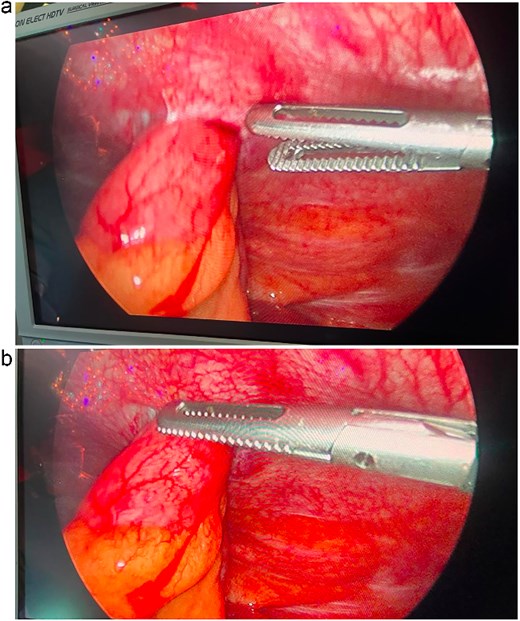

Diagnostic laparoscopy revealed small bowel herniation through the left lower quadrant port site with pelvic adhesions (Fig. 2). The bowel was viable, without ischemia or perforation. Reduction and adhesiolysis were performed, followed by reinforced fascial closure using EndoClose technique.

Intraoperative laparoscopic view demonstrating herniation of viable small bowel through the left lower quadrant port-site defect.